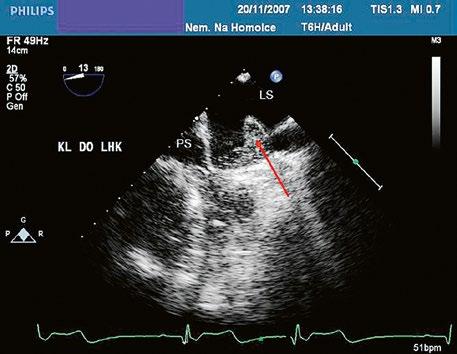

Poslechový nález systolického šelestu nad plicnicí s fixním rozštěpem 2. ozvy je nenápadný. Echokardiograficky je patrná dilatovaná a objemově přetížená pravá komora s paradoxním pohybem septa (Obr. 45.9), zkratový tok může být vidět i transtorakálně (TTE) (Obr. 45.10, Video 45.3, Video 45.7), ale suverénní diagnostickou metodou je jícnová echokardiografie (TEE), případně s 3DE zobrazením (Obr. 45.1, Obr. 45.2,

Obr. 45.10 TTE, čtyřdutinová apikální projekce s levo pravým zkratem na úrovni síní (šipka) při defektu septa síní typu secundum PK – pravá komora, LK – levá komora, LS – levá síň, PS – pravá síň